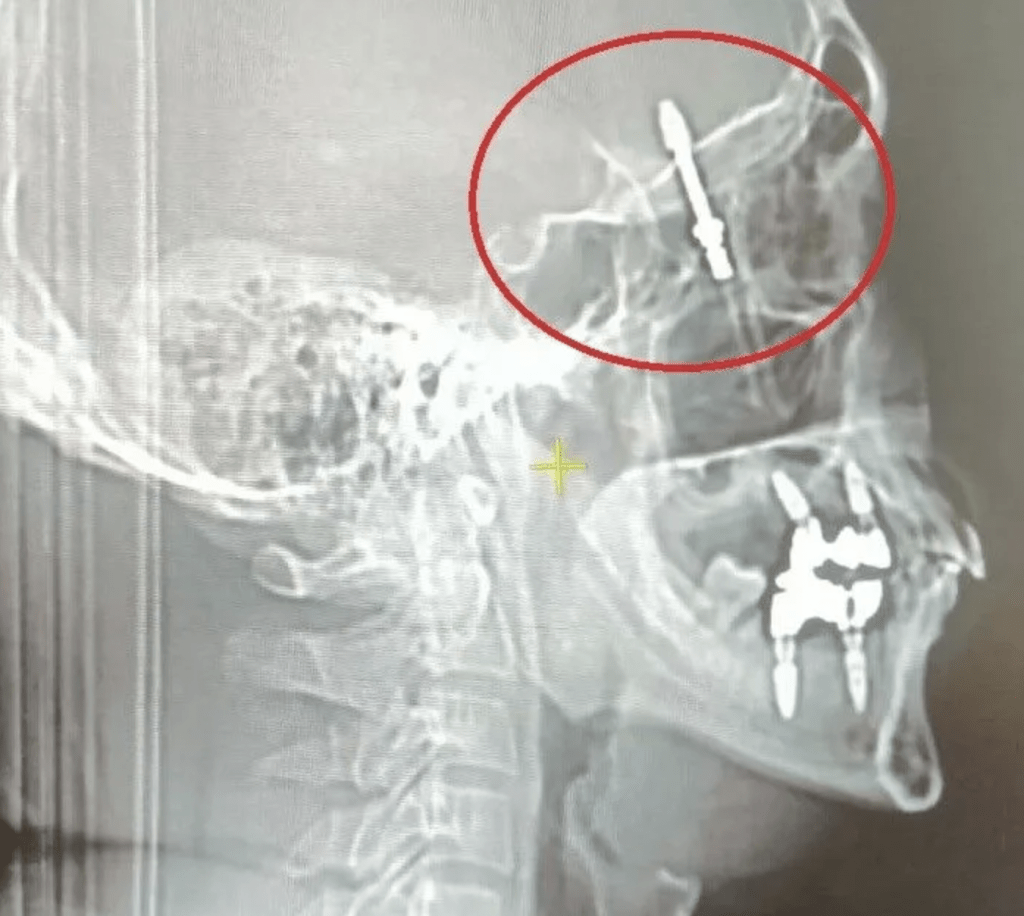

▲医生为化取出螺丝钉。

医生继续用力的转动螺丝,“螺丝就刺穿了我的颚骨,进入眼睛后面大脑和脊随液所在的区域”,他当场痛楚难当。据报,那颗螺丝钉直嵌入拉马赞的大脑中,牙医告知助手,手术中使用的设备坏了,随即为他拍了一张X光照片,并意识到问题的严重性后,马上将拉马赞送医院救治,然后自己便离开。

拉马赞又称,螺丝卡在他脑内一个非常关键的区域,手术前他被告知有重大风险,“当时我以为我以后不能再见到我的孩子,我向他们告别”。他现在入禀法院,控告有关牙医。